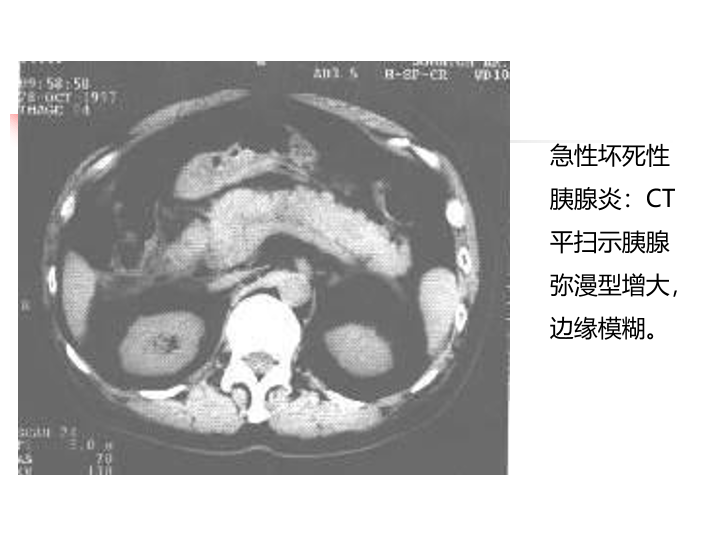

急性胰腺炎诊治